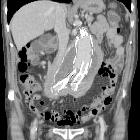

CT

Retroperitoneal fibrosis is visible as a soft tissue density mass located around the aorta and iliac arteries. Classically, it develops around the aortic bifurcation and spreads upwards where it can envelop the renal hila. It encases but does not invade or stenose the ureters or vessels. However, ureteric obstruction and venous thromboses can occur.

In early or active stages, variable enhancement can be seen with intravenous contrast while no enhancement may be seen in the quiescent disease.